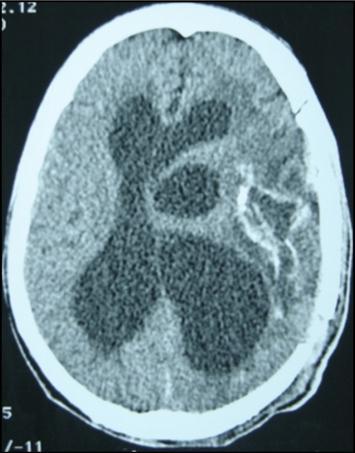

A 27 years-old male patient was admitted with 1 month history of headache, fever, short term memory lack, aphasia, right hemiparesis and seizures. He had liver hydatid cysts excised 8 years before and was treated with adjuvant medication (albendazole). The neurological examination revealed right central third cranial nerve palsy and hemi paresis, with Babinski sign positive, aphasia and papilledema on ocular fundus. The Glasgow Coma Scale was evaluated to 10/15 (E:3; V:1; M:6). A brain CT scan showed a large left temporoparietal intracerebral multiple and calcified hydatid cysts, important mass effect with midline shift about 7 mm following by an obstructive hydrocephalus (Figure 1). Other cysts were found in thalamic region (Figure 2). The Thoraco-abdominal CT scan showed multiple intra peritoneal hydatid cysts (Figure 3). A left temporo parietal craniotomy was performed in emergency. After corticectomy, using Arana-Iniguez technique, the appearance of the capsule suggested infected hydatid cysts with a purulent material which was aspirated. Numerous hydatid cysts were lifted away and several daughter vesicles were carefully removed without rupture (Figure 4). Macroscopically, the abscess wall appeared to be thick, calcified and tightly attached to lateral ventricular, so it could not be removed. The deep cyst overlying the third ventricle was left.in place. Microscopic examination demonstrated live scoleces, protoscoleces and multiple hooks. These findings are consistent with hydatid cyst (granulosis ecchinococcus) (Figure 5). Bacteriology examination found several white blood cells in the pus (neutrophilia) and infection by streptococcus pneumonia. This was consistent with infection. After surgery, the patient had medication (albendazole, specific antibiotherapy and phenobarbital). The inflammation assessment in the blood showed leukocytosis, a high C-reactive protein rate and increased erythrocyte sedimentation rate. Post operative CT scan was performed and showed the residual calcified capsule and decreased ventricular size (Figure 6). Clinical improvement was achieved after treatment. One month after the initial diagnosis, CT scan of the brain showed no recurrence and a physical examination revealed a neurologically intact, fully functional patient and eyes fundus normal. He was discharged and went to abdominal surgery two months later with complete intra abdominal cysts removal. Albendazole treatment was continuing for six months and radiological exploration was performed by brain MRI with spectroscopy at three and six month later. This showed that infection had resolved and the deep cyst overlying the third ventricle is less spherical (Figure 7, Figure 8). Four years later, the outcome was good.

Figure 6.post operative CT scan showing the residual capsule.